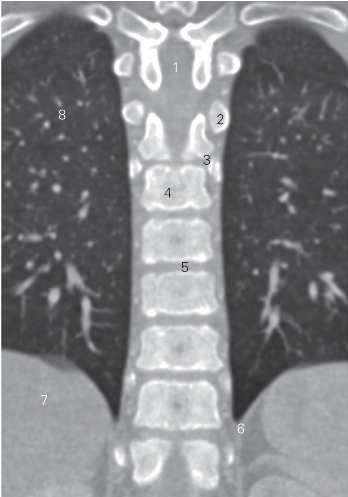

图2-2 经胸段脊柱前份的冠状断层CT图像(软组织窗)

1 椎管 vertebral canal 2 第3肋肋头 3rd costal head

3 肋头关节 joint of costal head

4 第4胸椎椎体 4th thoracic vertebral body

5 第5胸椎间盘 5th thoracic intervertebral disc

6 左膈脚 left crura of diaphragm

7 肝 liver 8 右肺 right lung